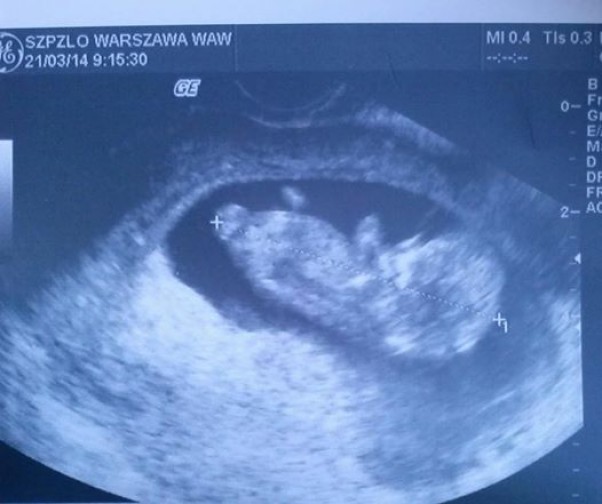

nasze pierwsze wyraźne zdjęcie-mamy 14 tygodni,serduszko bije jak szalone i macham do Was rączkami i nóżkami :) nie mam jeszcze płci widocznej ale jestem zdrowe :)